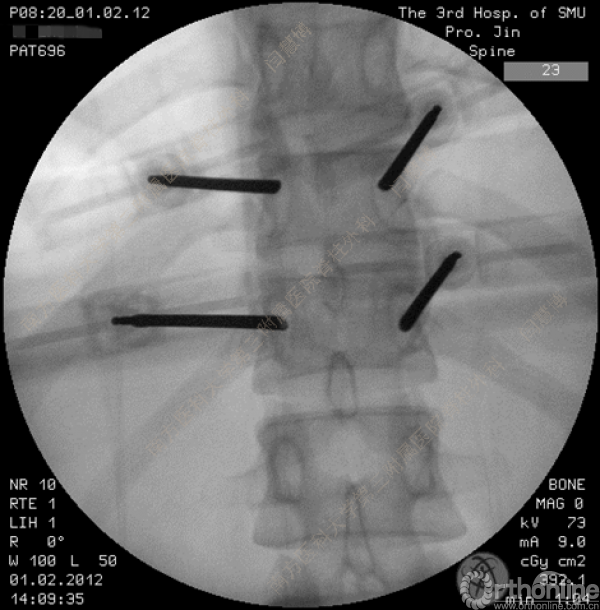

胸腰椎骨折是指由于外力造成胸腰椎骨质连续性的破坏,在如车祸、高处坠落等意外事故中,是最常见的脊柱损伤。老年患者由于本身存在骨质疏松,甚至有可能因为一些如滑倒、跌倒等低暴力因素导致胸腰椎骨折。胸腰椎骨折患者常合并神经功能损伤,且由于致伤因素基本为高能损伤,常合并其他脏器损伤,这为治疗带来了极大的困难和挑战。针对胸腰椎骨折,南方医科大学第三附属医院闫慧博教授介绍了他们运用微创方法治疗的经验。